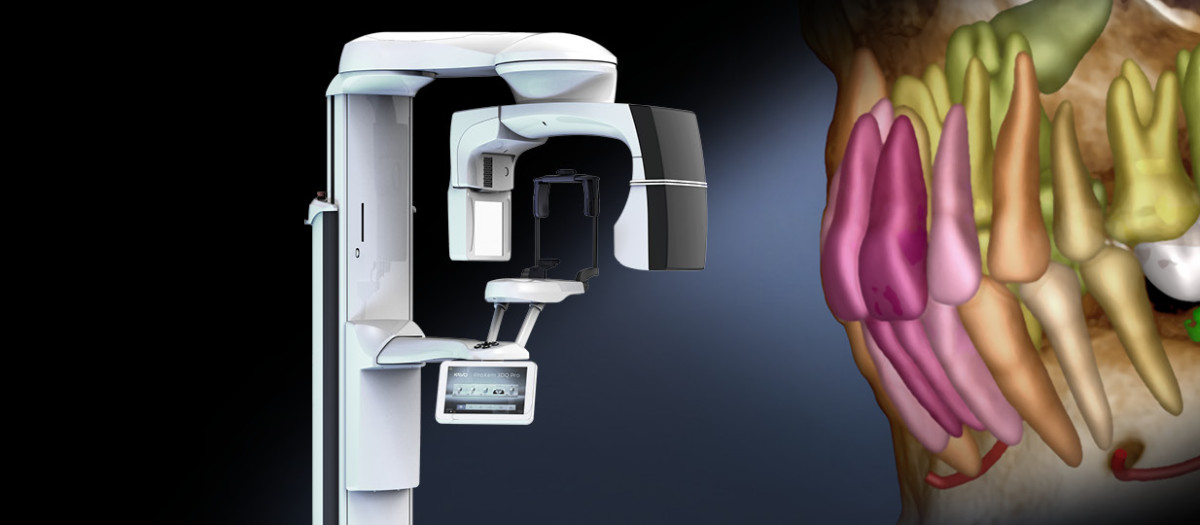

Captures every detail.

Disfrute de la combinación perfecta entre la tecnología de rayos X moderna y el soporte de software inteligente: la tecnología de imagen KaVo ProXam y las herramientas basadas en IA de Romexis permiten obtener imágenes que muestran más allá de lo obvio.